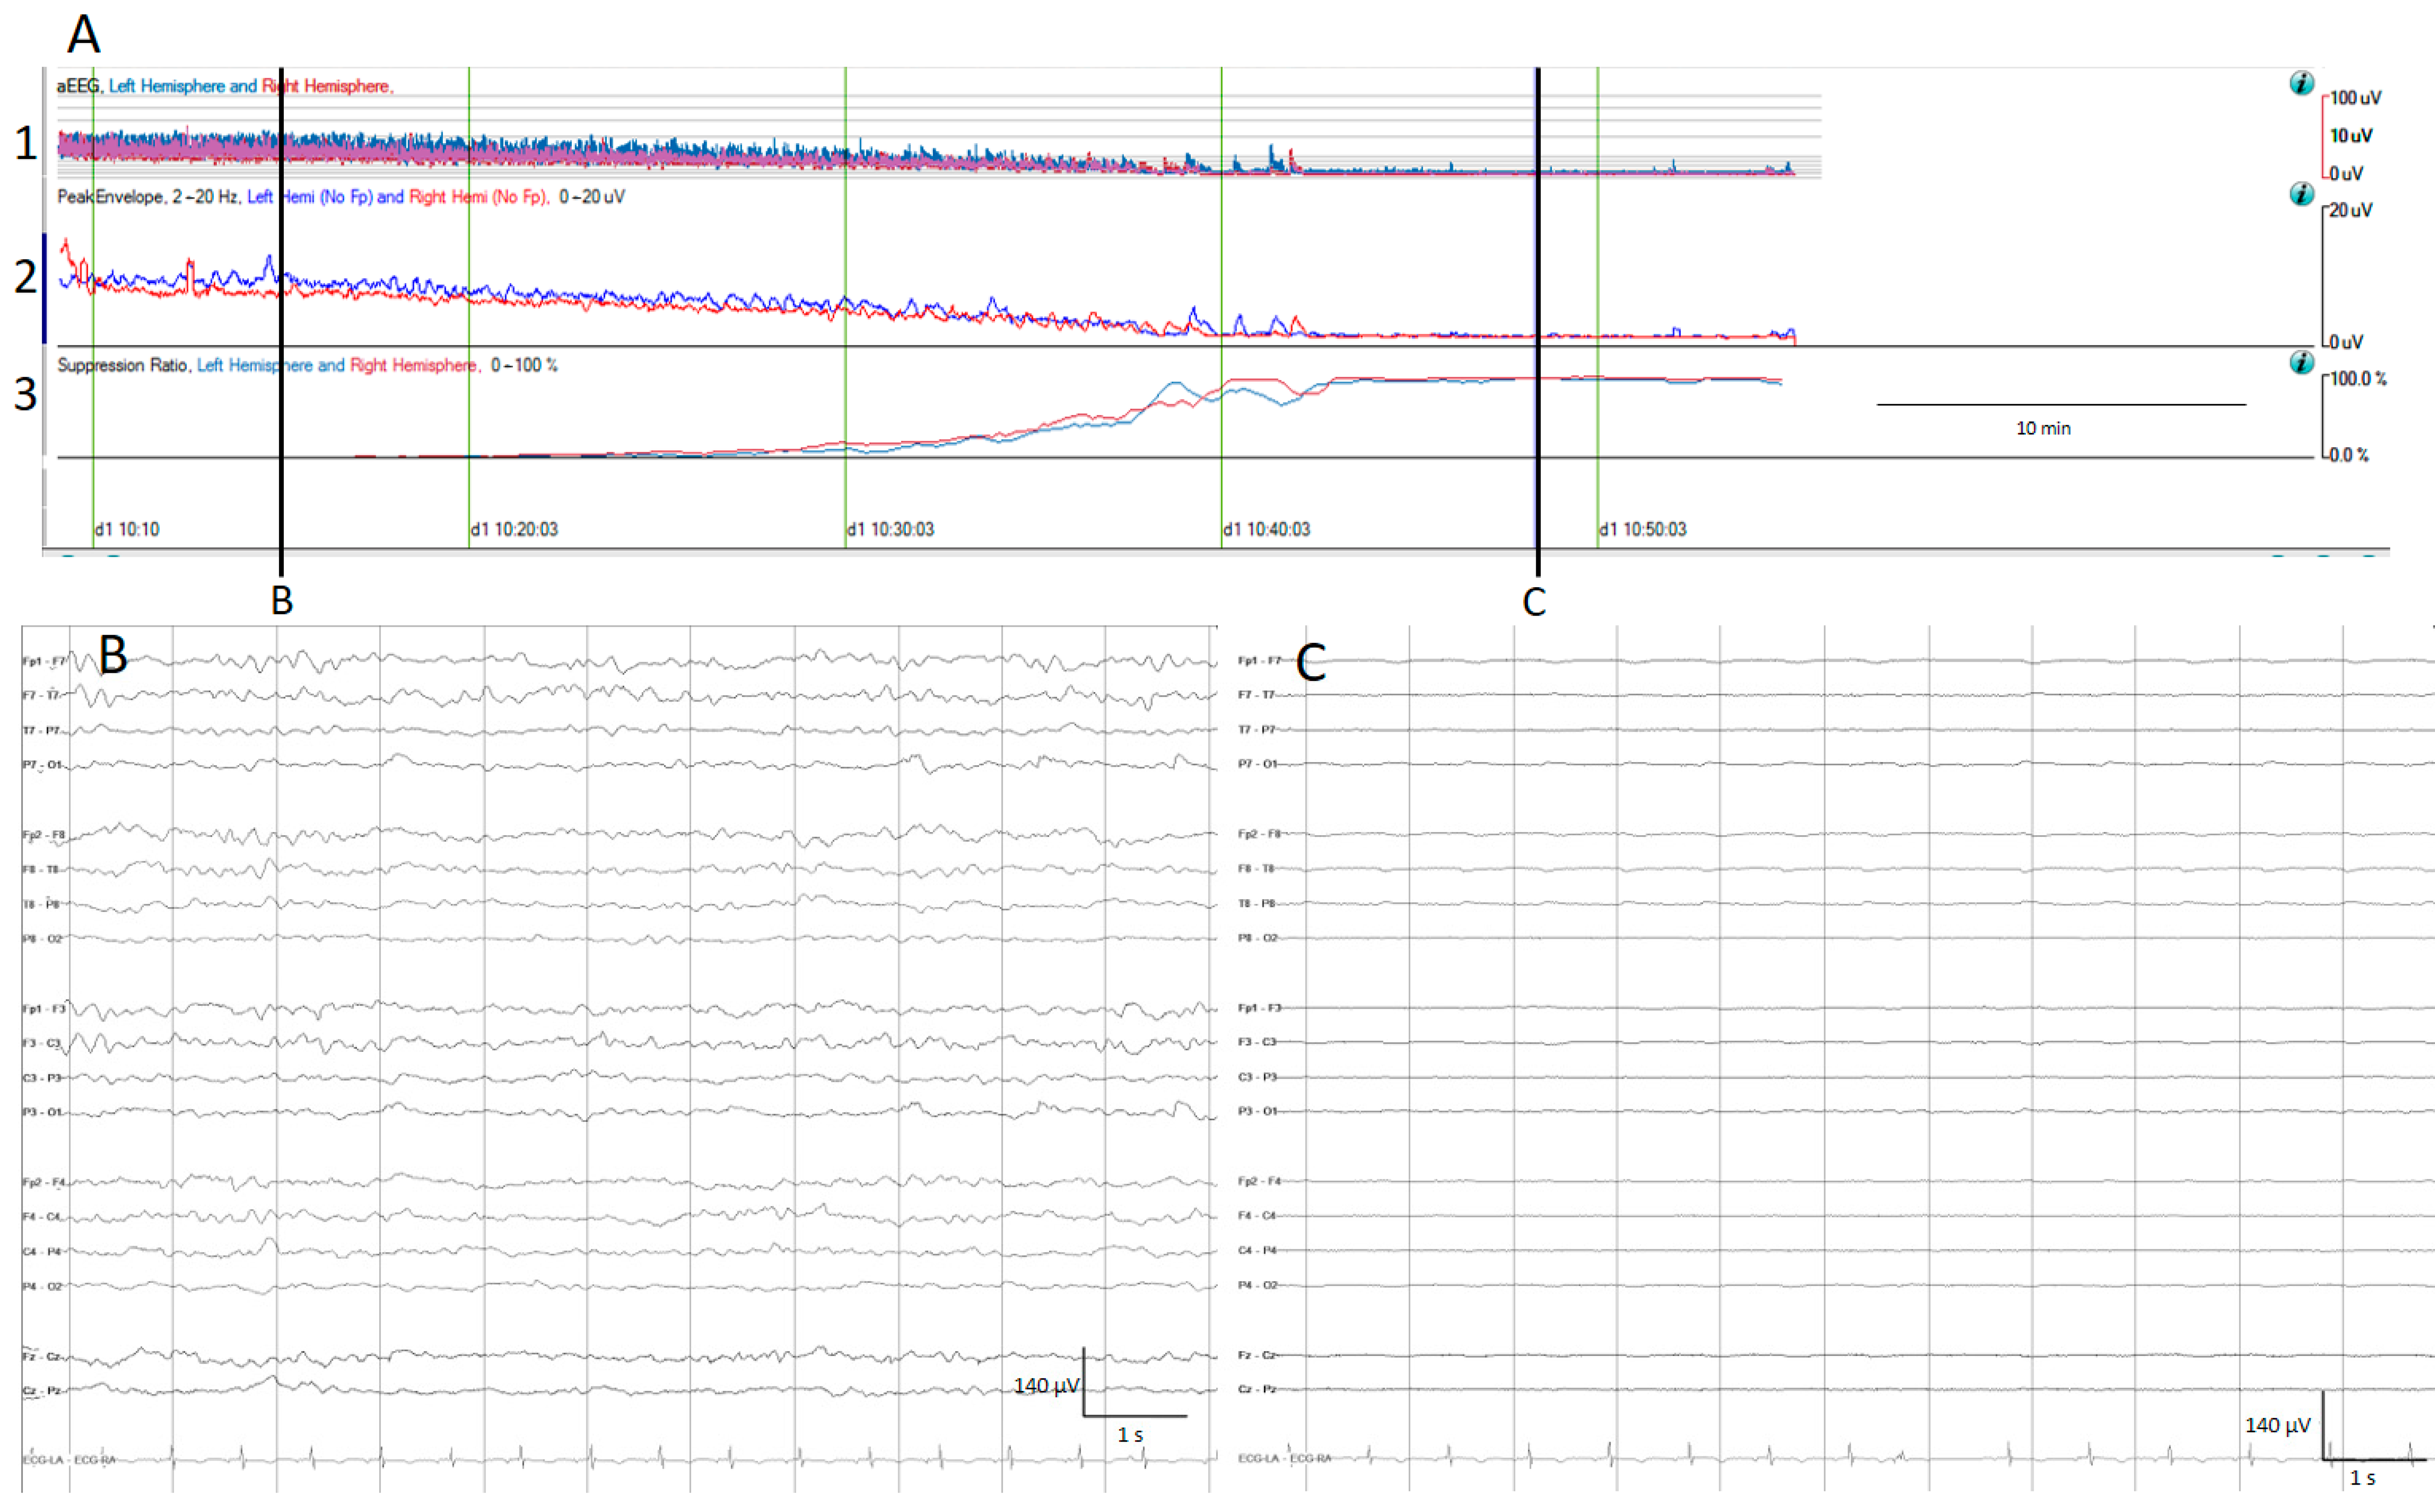

Figure 1.

(A) qEEG amplitude measures. For all qEEG measures, the left hemisphere is depicted in blue and the right hemisphere in red; time is represented on the x-axis and amplitude in different scales on the y-axis. 1. Amplitude integrated EEG (aEEG): the maximum and minimum amplitude of each epoch connected with a vertical line is depicted using a semi-logarithmic scale (linear from 0 to 10 µV, and logarithmic from 10 to 100 μV). 2. Envelope trend: the peak amplitude from each epoch is plotted. 3. Suppression percentage: shows the percentage of suppression ranging from 0% (no suppression) to 100% (complete suppression). At the beginning, the raw EEG recording (B) and all amplitude EEG trends show normal amplitudes, and progressively the amplitude decreases as is depicted by the drop on the aEEG, peak envelope, and rise in suppression percentage. At the end of the recording, there is a complete suppression of the EEG (C).

The aEEG is a trend which has been used for a quite long time in neonatologist units [21]. After filtering, rectifying, and smoothing the raw EEG, the maximum and minimum amplitude for each epoch connected with a line is plotted on the y-axis, using a semi-logarithmic scale (linear from 0 to 10 μV, and logarithmic from 10 to 100 μV); practically, this means the low amplitudes are magnified [13,14] (Figure 1).

The envelope trend is another amplitude-related trend; unlike the aEEG, the envelope trend only plots one value for each epoch, either the median amplitude (median envelope trend) or the peak amplitude (peak envelope trend). While the median amplitude is less susceptible to artefacts, it may overlook small amplitude seizures, contrary to the peak envelope trend [13].

The suppression percentage indicates the percentage of the time EEG is suppressed within an EEG epoch; for this purpose, usually the detection of suppression is setup to an amplitude less than 5 μV for more than 0.5 s. In Persyst software (In this present work, versions 13 and 14 were used), this setup can be customized. Therefore, suppression percentages range from 0%, indicating continuous cerebral activity, to 100%, indicating complete suppression [13] (Figure 1).